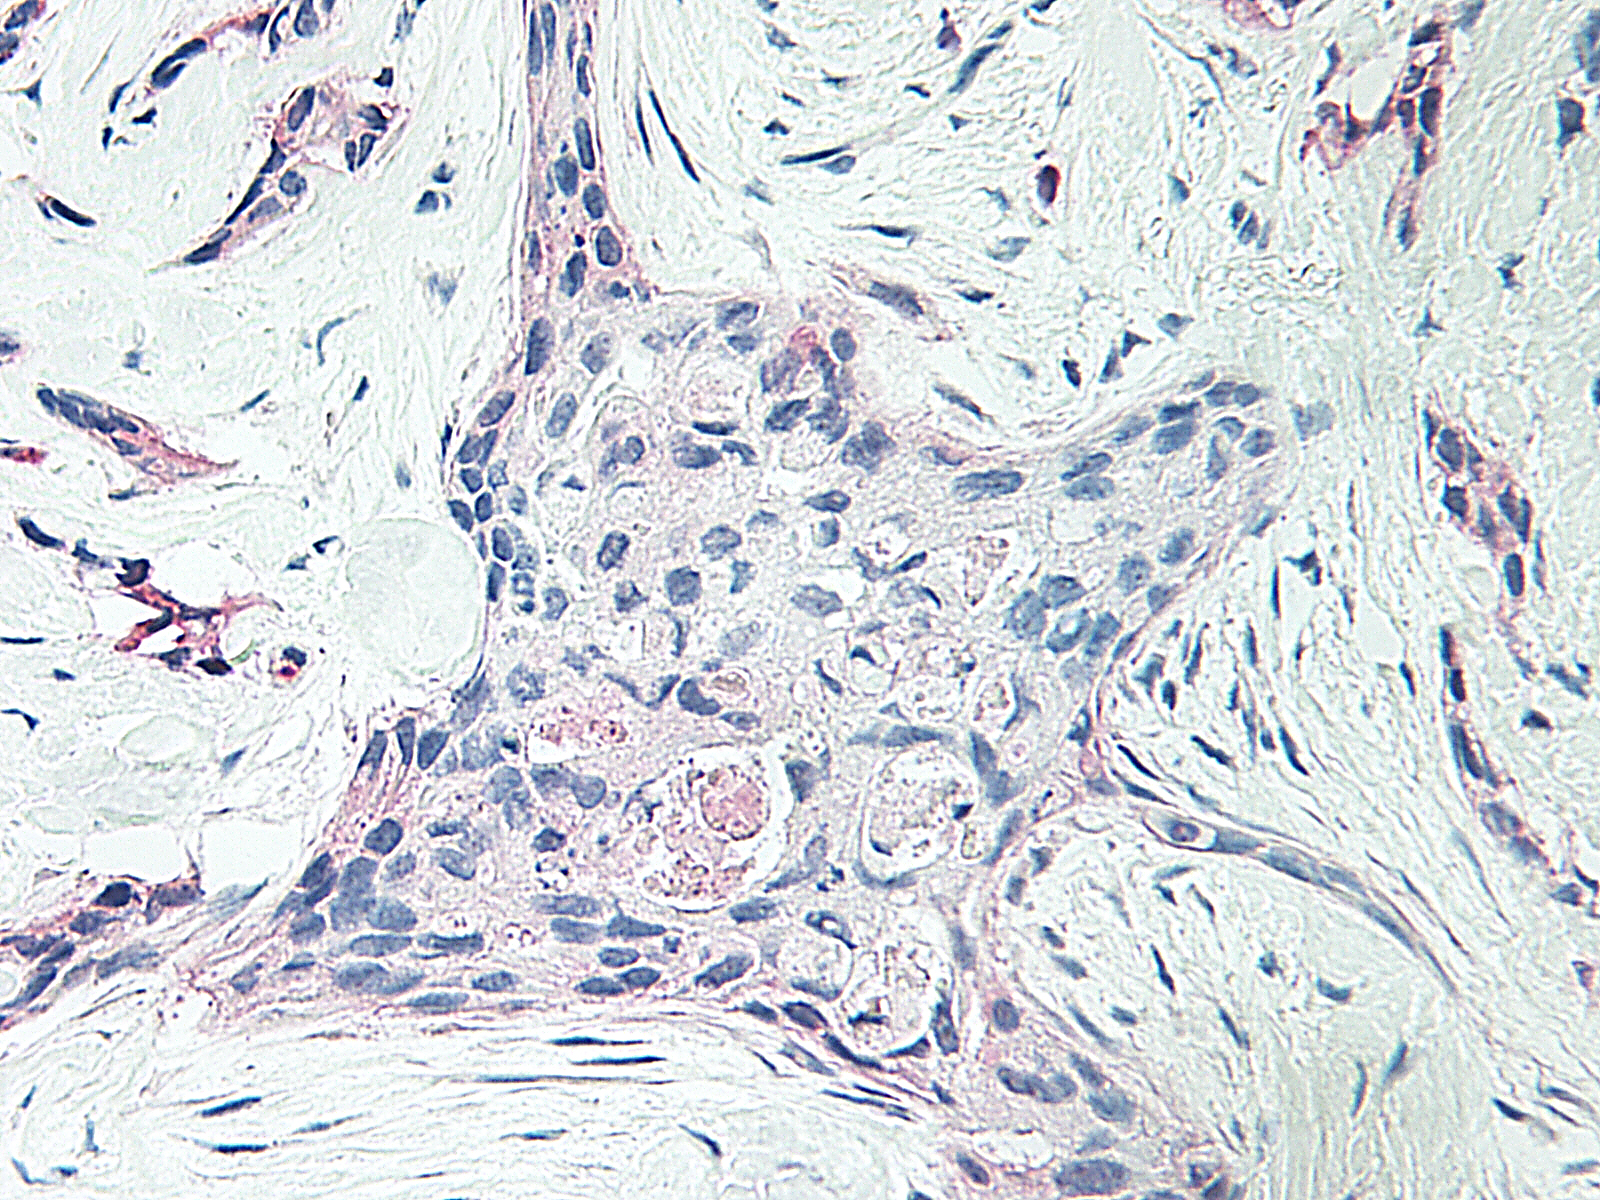

ARG56640 anti-CXCL4 / PF4 antibody IHC-P image

Immunohistochemistry: Formalin-fixed and paraffin-embedded sections of Human breast malignant ductal adenocarcinoma. The recommended ARG56640 anti-CXCL4 / PF4 antibody concentration is 1.0 µg/mL - 2.0 µg/mL with an overnight incubation at 4°C. An alkaline phosphatase-labeled polymer detection system was used with a red chromogen. Antigen Retrieval: Boil tissue section in Sodium Citrate buffer (pH 6.0) followed by cooling at RT for 20 min.